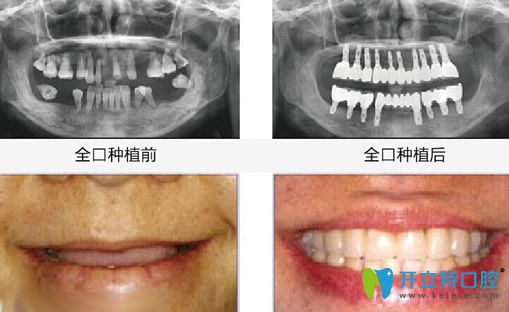

【全口牙缺失種植效果】

湛江致美口腔全口牙種植牙案例效果

種植牙前:全口牙齒缺失;

種植牙顧客評(píng)價(jià):由于牙齒掉光了,平時(shí)只能吃些稀飯和面條之類(lèi)的食物,所以身體也不如以前好了,在女兒的帶領(lǐng)下到湛江致美做了全口牙種植牙,沒(méi)想到當(dāng)天回家就能吃東西,而且看著也和真牙沒(méi)什么兩樣!